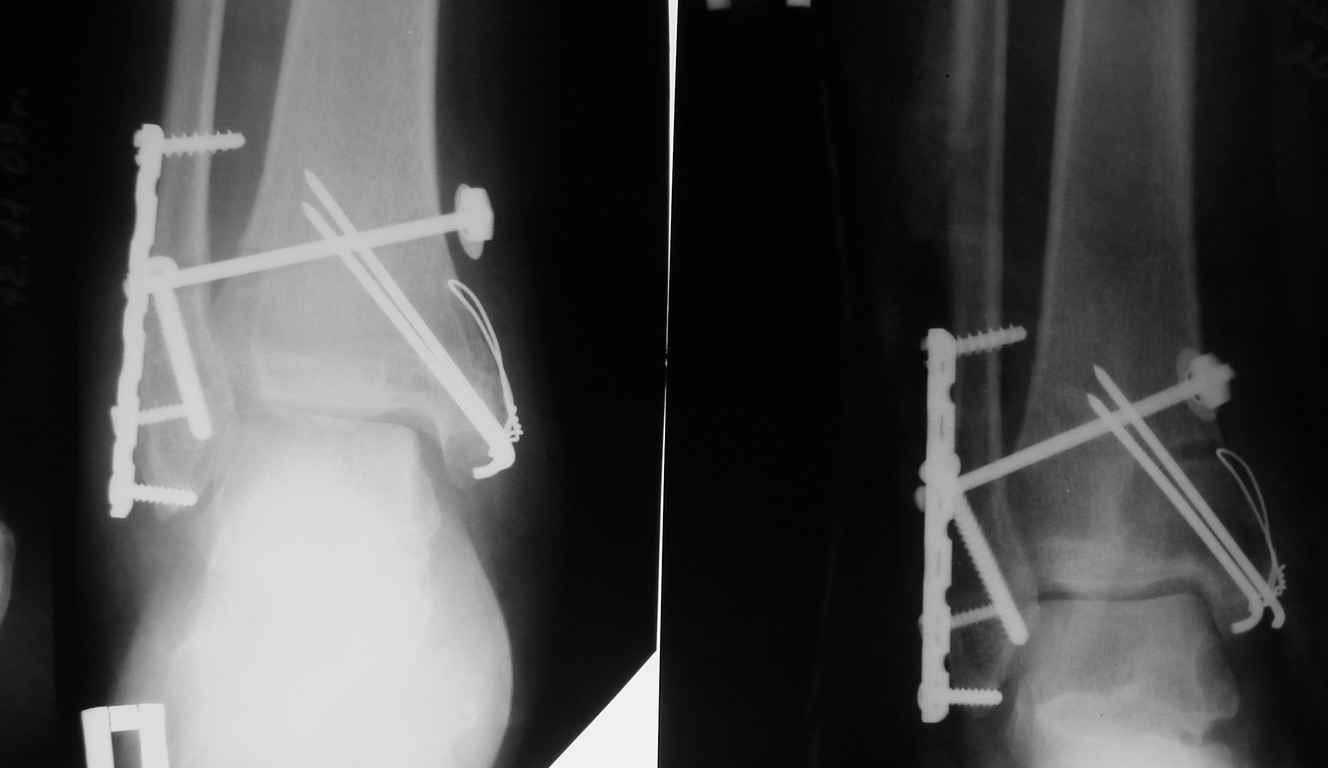

Травма медиальной лодыжки. Разрез выполняется на внутренней стороне ноги вдоль стопы. Удаляются кровяные сгустки и мелкие осколки, после чего поврежденные участки фиксируются металлическими спицами.

Двойной перелом. Для фиксации костей используется остеосинтез с применением различных конструкций, ограничивающих подвижность поврежденной лодыжки. Операция требует разрезов с обеих сторон стопы.

Перелом с вывихом внутрь. Операция включает разрез кожи и рассечение сухожилий голеностопа. Кости фиксируются штырями и пластинами, после чего мягкие ткани зашиваются.

Травма задней части голени с смещением. Это экстренная операция, при которой разрез выполняется вдоль ахиллова сухожилия. Удаляются сгустки крови и мелкие осколки, крупные фрагменты крепятся к большеберцовой кости с помощью винтов.

После всех операций на лодыжке накладывается гипс для обеспечения стабильности и правильного заживления.

Удаление металлических пластин и винтов обычно происходит через 4-6 месяцев, реже — через год после операции, и только при условии надежного сращивания костей. В некоторых случаях инородные тела могут быть удалены раньше, если наблюдаются отторжение металлических конструкций, неправильное сращение, недостаточная фиксация или нагноение в области перелома. После повторной операции полное восстановление тканей занимает несколько месяцев.

Удаление металлических элементов не требуется, если они находятся в организме более трех лет, при глубоком врастании или в пожилом возрасте пациента. Металлоконструкции могут оставаться в лодыжке также при сложных переломах, когда нервные окончания и сосуды расположены близко к фиксаторам.